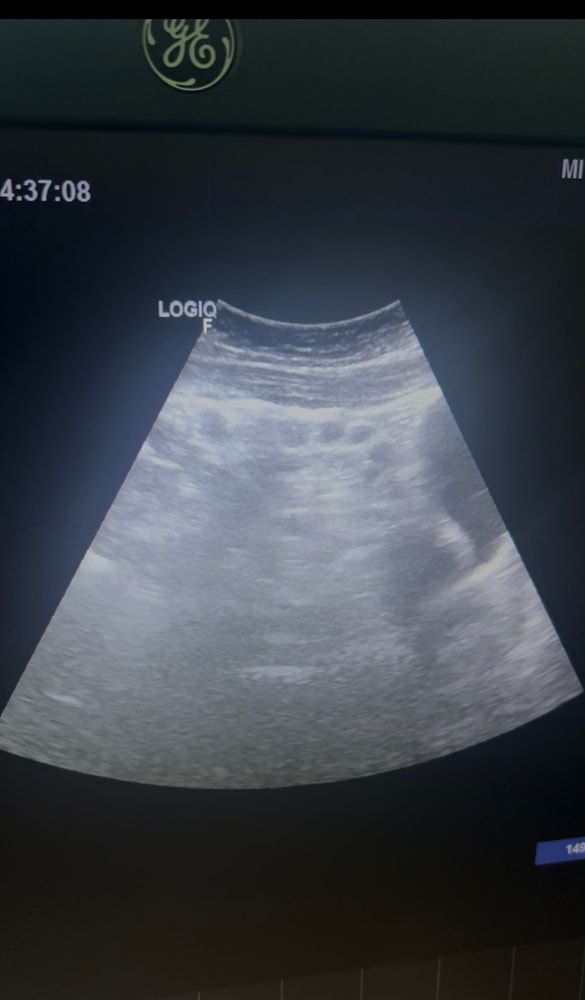

На обоих снимках вроде как яичники с фолликулами. Чтоб увидеть ЖТ надо смотреть кровообращение. Если есть круговое, то это ЖТ. По этому по этим снимкам не определить, увы